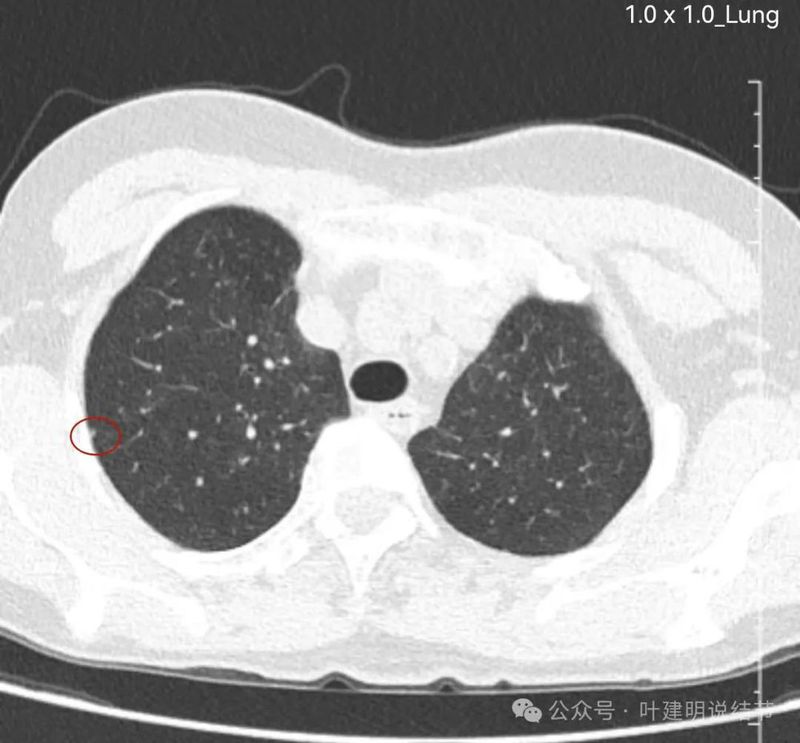

先来看两肺多发病灶的情况:

胸膜下微小结节,轮廓较清,才1-2毫米,可供分析的影像特征太少,反正先随访。

胸膜下结节两处,也是密度较高,边界较清,但还很小。